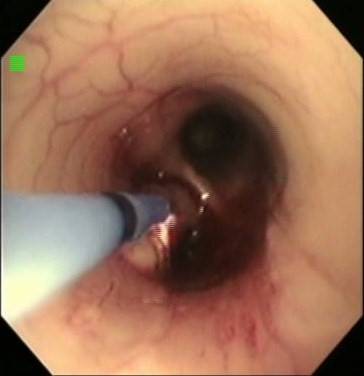

気道内肉芽や気道内腫瘍の失活や縮小に気管支鏡下処置として近年医学領域で使用されるようになってきた6。主な作用は非接触凝固である。凝固深度は浅く制限されている。レーザー治療の強力な蒸散作用に比べ組織縮小効果は小さいが、出血や穿孔事故の可能性は低いので安全性が高い。接線方向の焼灼も可能であり(図6)、犬猫の狭い気道腔内での処置に有利である。発煙も少ない。獣医領域でも、ステント内肉芽処置、気道内腫瘍、気道内止血凝固などに適用される(図7)。レーザーほどではないが、処置中の酸素濃度が高い(100%)と出火の可能性が指摘されている7。少なくとも気道内酸素濃度を40%未満、処置中酸素投与は中止し大気濃度とし、出力は40W、ガス流量0.8L/minという環境で気管支鏡下治療に用いられることがすすめられている7。レーザー治療に準じると、酸素投与から大気下換気にして30-40秒待ってから処置を開始し、1秒以上の連続照射をしないようにすすめられる8。

図7 左主気管支から突出する気道内腫瘍に気管支鏡下APC焼灼を行っているところ。